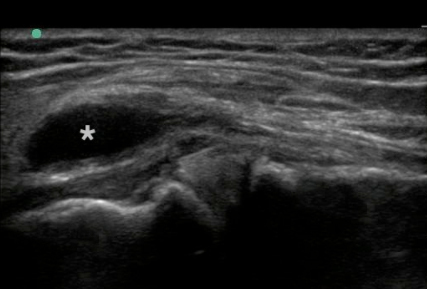

Knee Medial Meniscus Cyst 1 Image

Asterisk: Peri-Meniscal Cyst